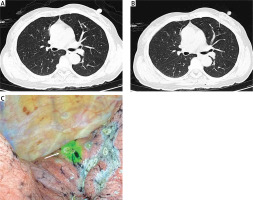

The needle puncture procedures were identical to those for the HW localization procedure. After the needle tip was appropriately positioned, the IG agent (2.5 mg/ml, 0.3 ml) was slowly injected. Postoperative CT imaging was used to detect any procedure-related complications.

VATS wedge resection (WR) procedures were performed under general anesthesia within 3 h following localization. A 3–5 cm incision in the chest wall was made, after which WR was performed based on HW visualization or IG fluorescence (Photo 2 C). The WR range was at least 2 cm from the localized area of the lung. Rapid intraoperative pathological analyses of the resected LN sample were then conducted. When LNs were confirmed to be invasive lung cancers, lobectomy and systematic lymph node resection were performed. The systematic lymph node dissection was performed according to the National Comprehensive Cancer Network guideline [13].